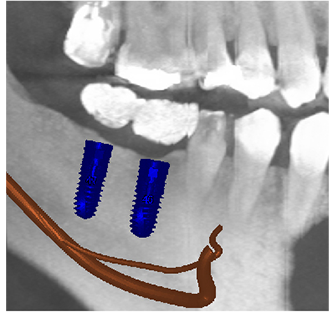

当院では安心安全なインプラント治療をより確実に行うために、すべてのインプラント治療で3Dコンピューターシミュレーションシステム「シンプラント プロ」で歯科CT画像からデータ解析を行い、サージガイドを作成するコンピューターガイデッド インプラント治療を行っています。

シンプラント プロとは

一般的なレントゲン写真のみでの術前診断では、平面的な写真画像のため、骨の厚みや神経の走行などを立体的に見ることはできませんでした。

そのため手術中に骨の状態を直接見て手術を行う必要があり、術者の経験や勘頼りになりやすく計画していた位置にインプラント手術が行えないということもあります。

歯科用CTは、顎の骨の断面像を見ることができ、一般的なレントゲン写真よりも多くの情報を得ることが可能です。しかし、実際の手術ではそのCT画像を参考にして、フリーハンドでインプラント手術を行うため、やはり術者の経験や勘頼りになりやすく計画した位置からずれてしまうこともあります。

シンプラント プロのコンピューターガイデッド インプラント治療では、歯科CT画像から3D画像を構築し、骨の厚みや神経の走行などを視覚的に診査できます。

そして嚙み合わせ、骨の厚みや神経の走行からからみて三次元的に理想的なインプラントの位置を画像上でシミュレーションすることができます。これにより手術を行う前に安全で理想的なインプラントの位置を決定することが可能になりました。

画像は患者様に見てもらうことで予定するインプラントの施術後のイメージを画像で確認できます。

歯科CTデータからシンプラントで3D画像を表示して骨の厚みや神経、血管の走行を検査します

噛み合わせ、骨の厚みや神経の走行からみて理想的なインプラントの位置を決定

インプラント治療の仕上がりのイメージは画像で患者様も視覚的に確認できます